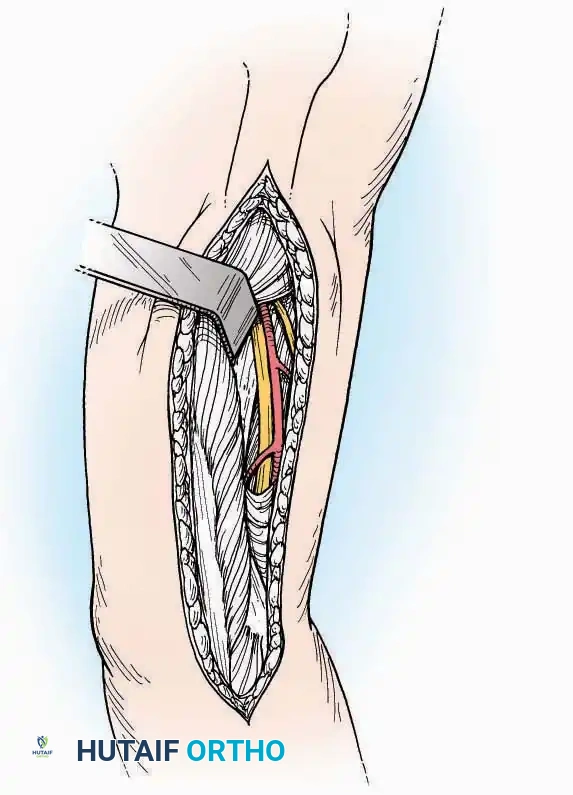

Medial Approach

Indications: Fixation of sustentaculum tali fractures, medial process fractures, or excision of medial tarsal coalitions.

Positioning: Supine with the hip externally rotated and knee flexed (figure-of-four position).

Surgical Technique:

* Incision: Begin 2.5 cm anterior and 4 cm inferior to the medial malleolus. Carry it posteriorly along the medial surface of the foot toward the Achilles tendon.

* Superficial Dissection: Divide the fat and fascia to define the inferior margin of the abductor hallucis muscle.

* Deep Dissection: Mobilize the abductor hallucis muscle belly and retract it dorsally to expose the medial and inferomedial aspects of the calcaneal body.

* Plantar Exposure: Continue distally by dividing the plantar aponeurosis and the muscular attachments to the calcaneus, or strip them subperiosteally with an osteotome.

* Neurovascular Warning: Meticulously identify and protect the medial calcaneal nerve and the nerve to the abductor digiti minimi (first branch of the lateral plantar nerve), which are highly vulnerable during inferior retraction.